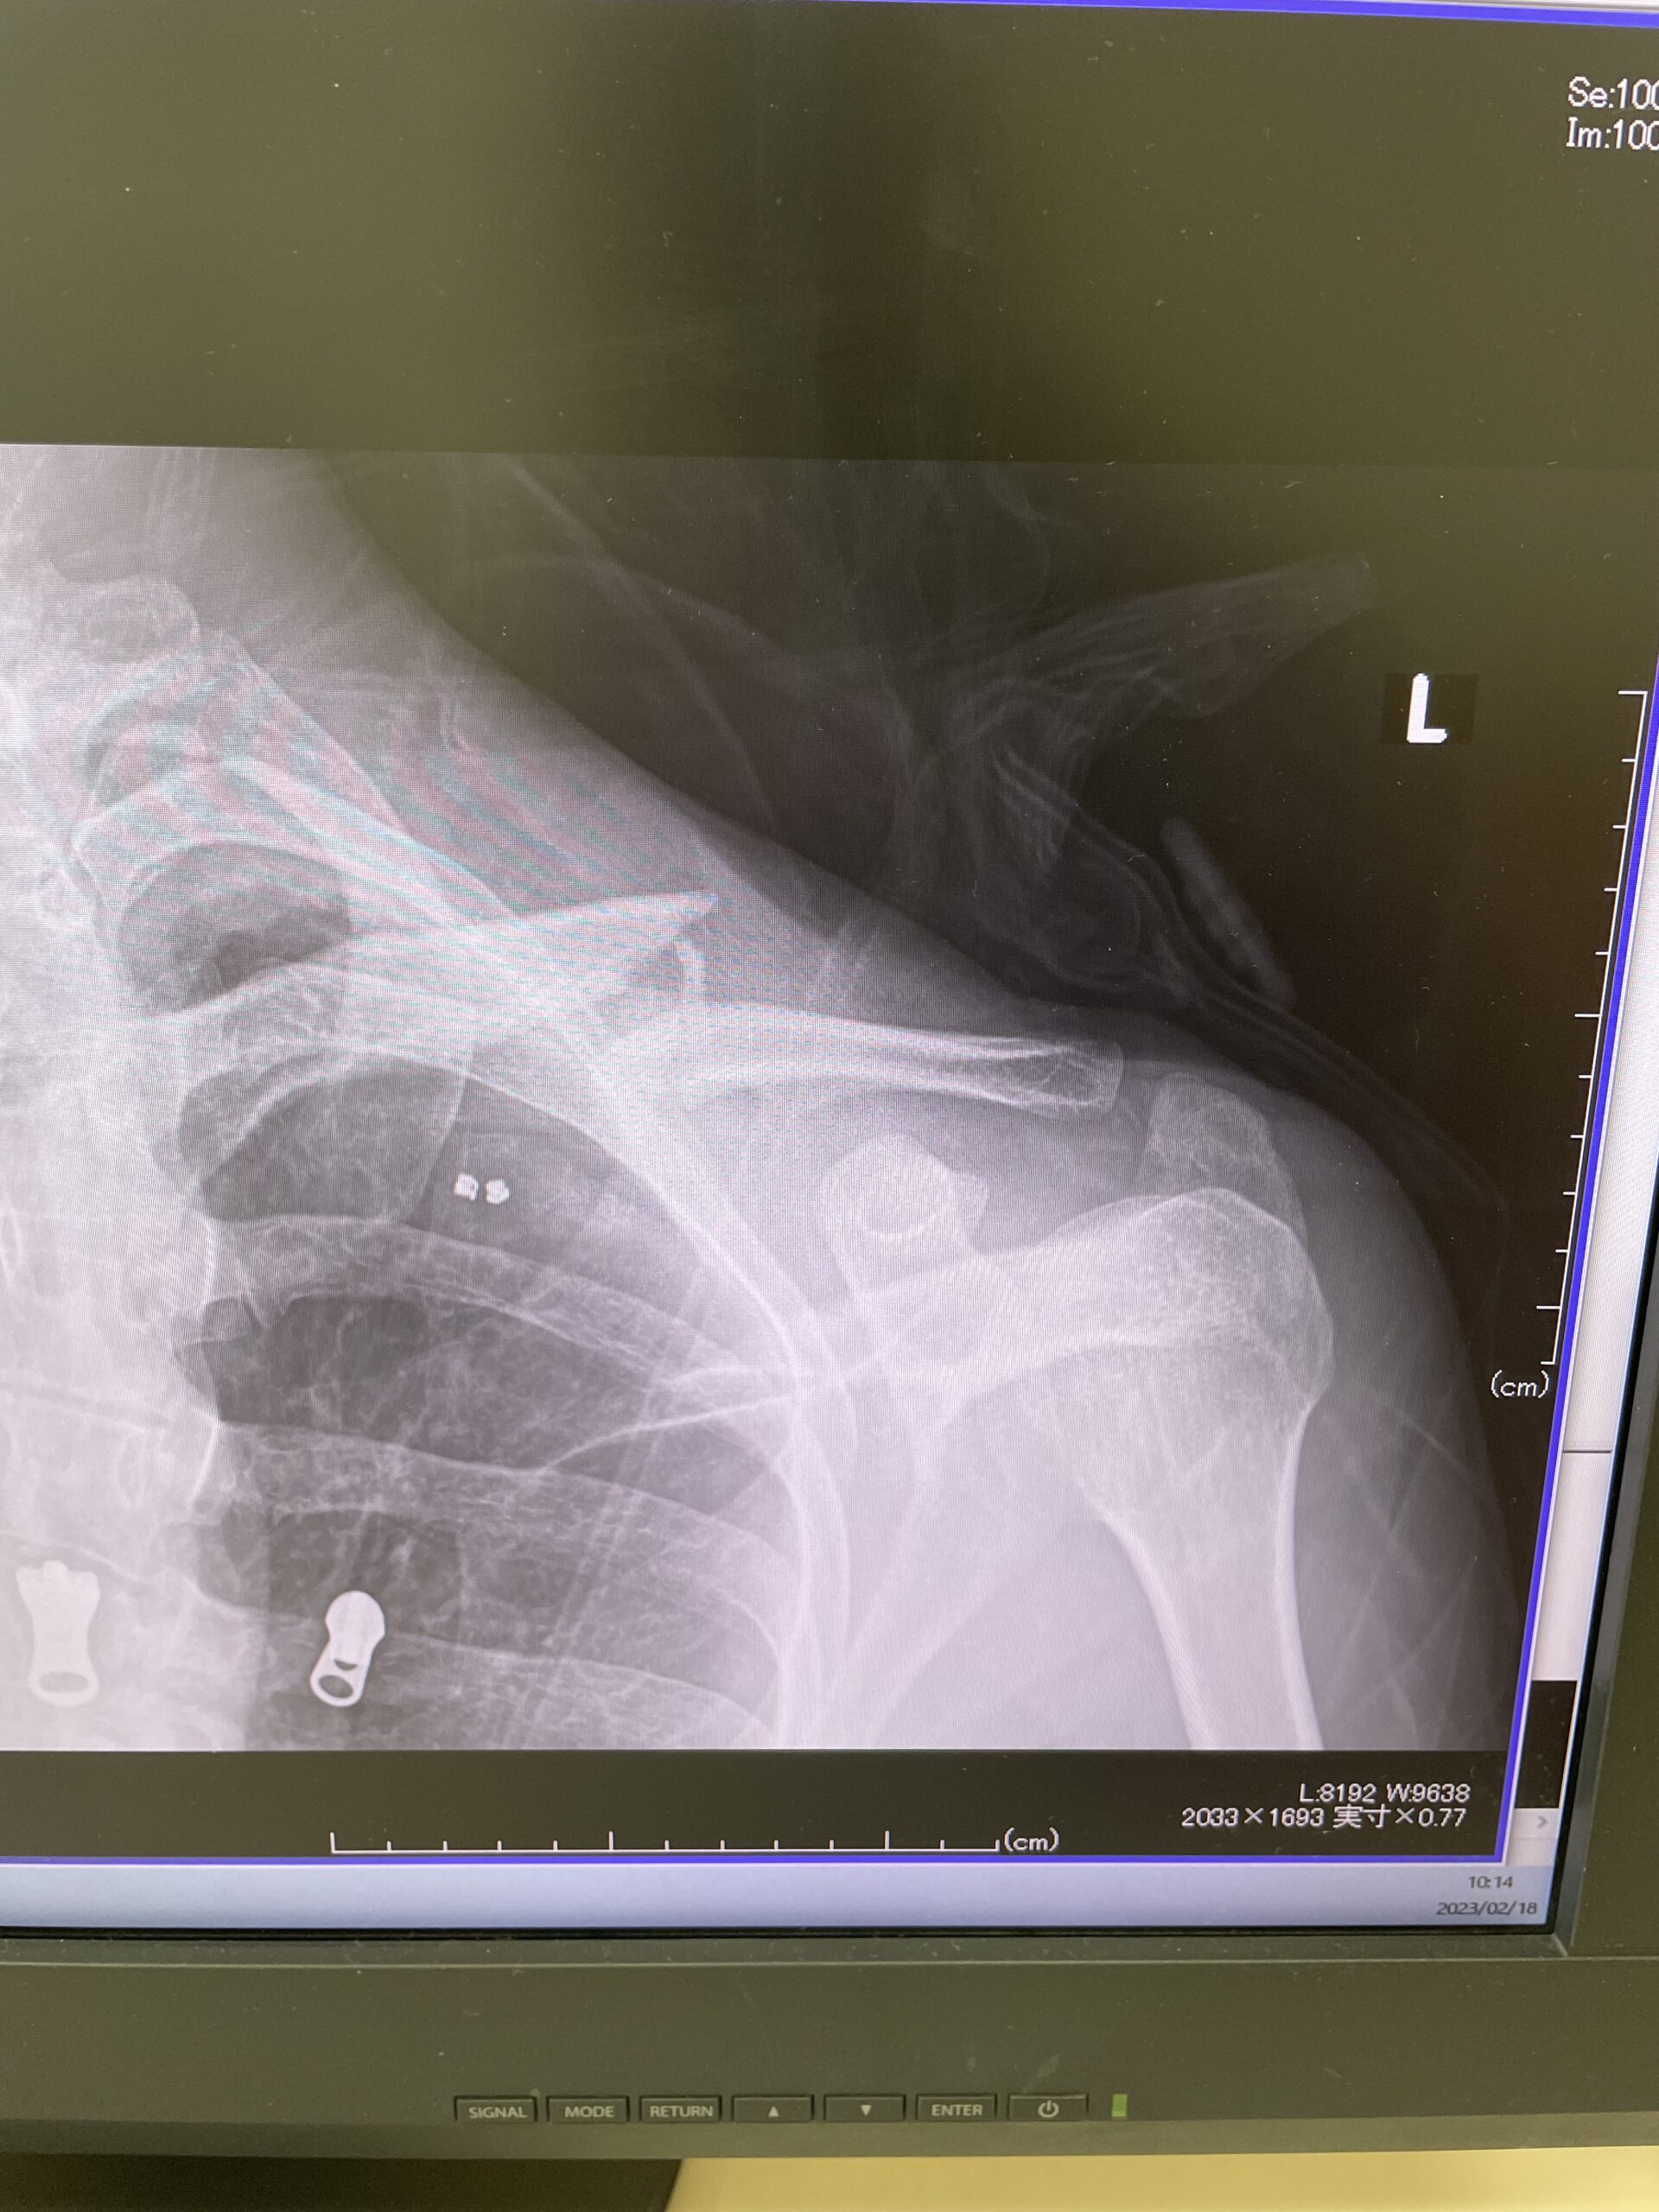

「鎖骨骨折とは」

6月末に落車で鎖骨を折った上野の復帰戦なわけですが

鎖骨を折るってのは競輪選手にはよくある骨折の部類

今は違うかもしれないが川崎に競輪選手の鎖骨骨折の御用達の病院があるのですがそこで自分も鎖骨折ったときに手術しました。